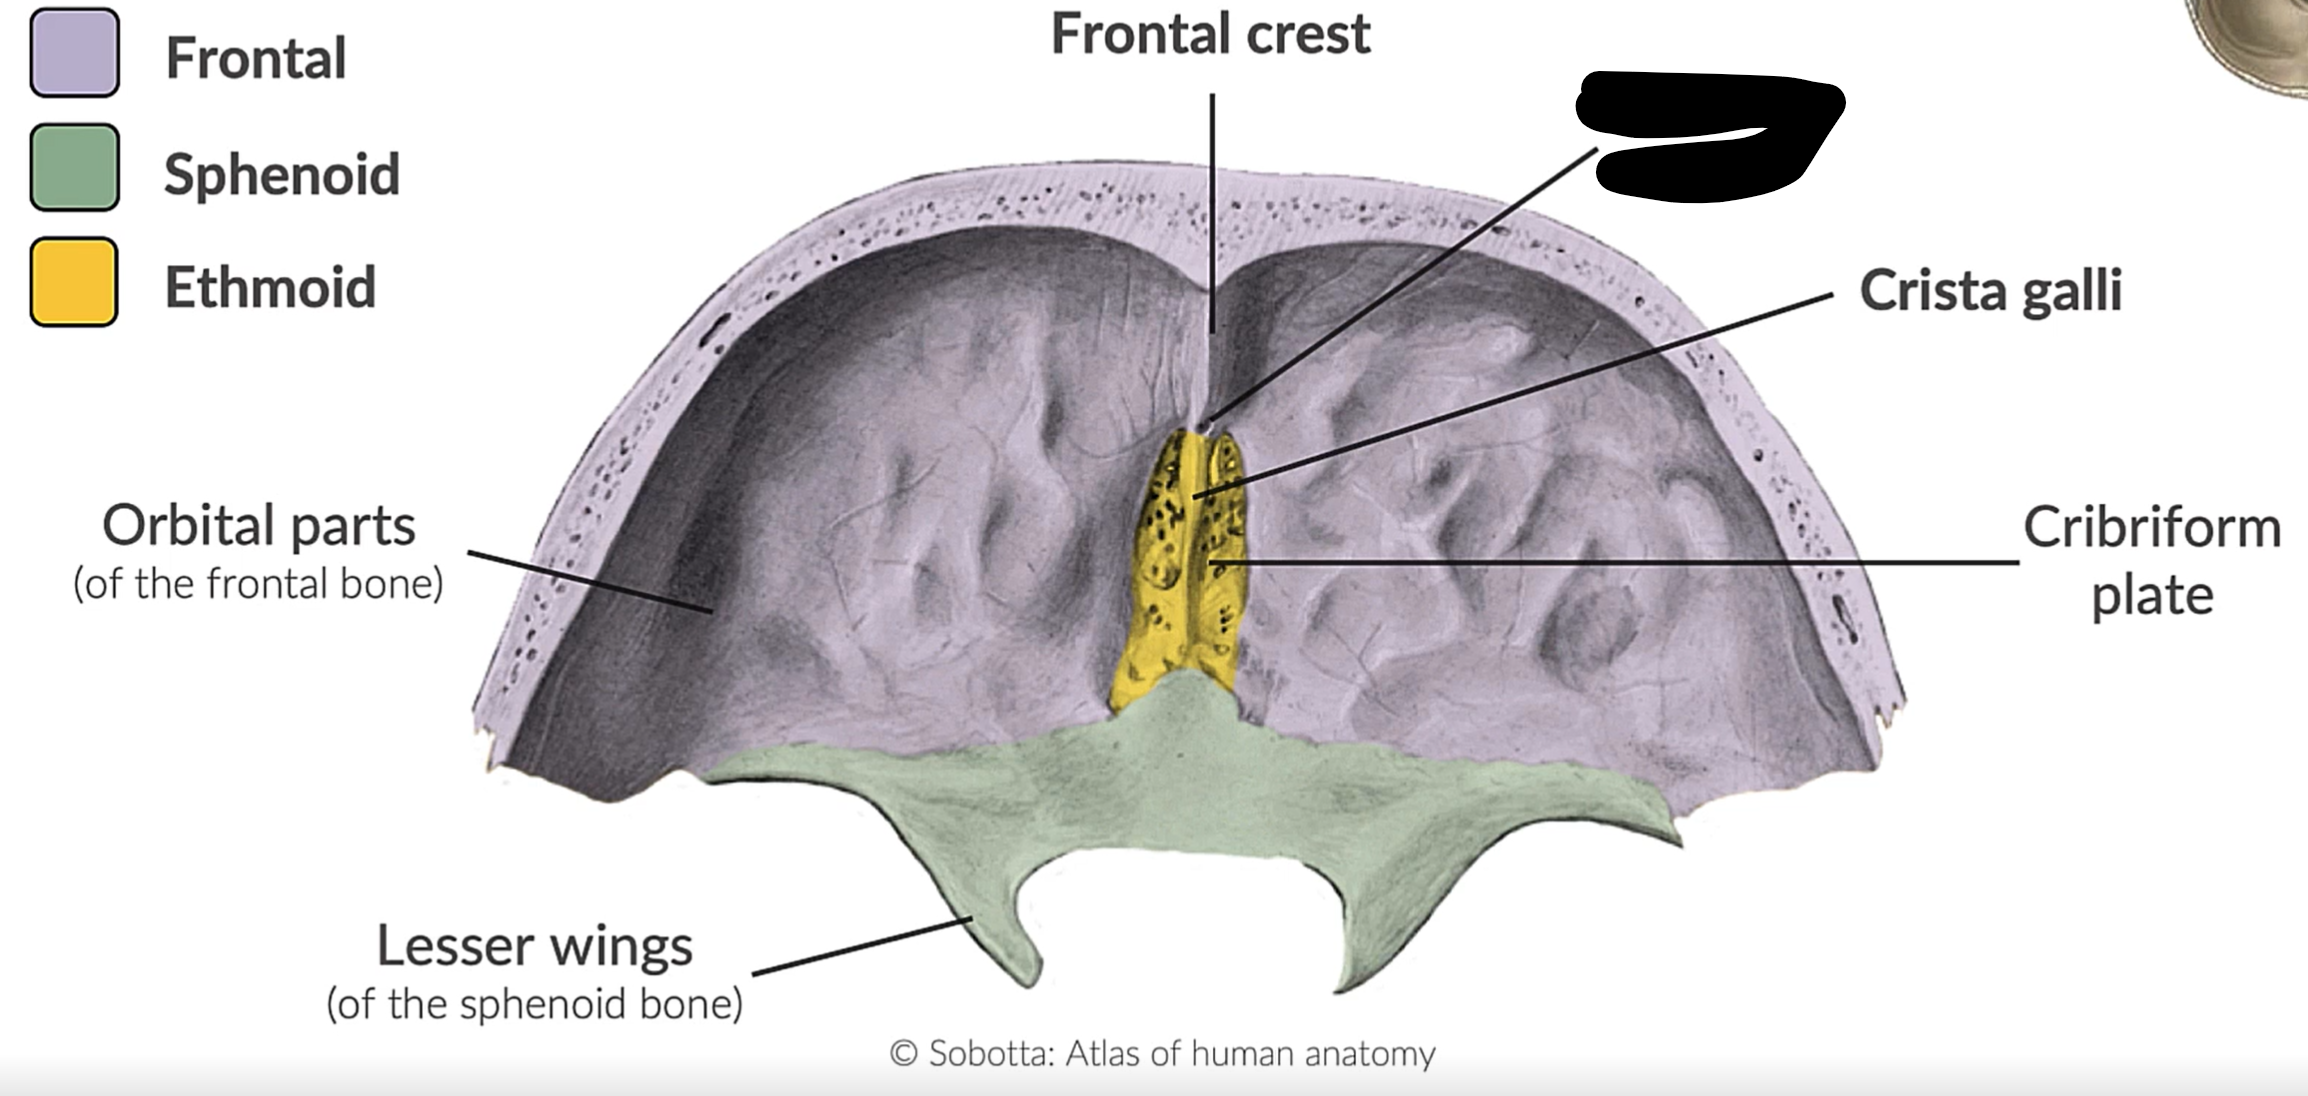

What bones form the anterior cranial fossa?

Frontal, ethmoid and sphenoid

What is this?

Anterior cranial fossa

What is this?

Cribriform plate

NN

Crista galli

Foramen caecum